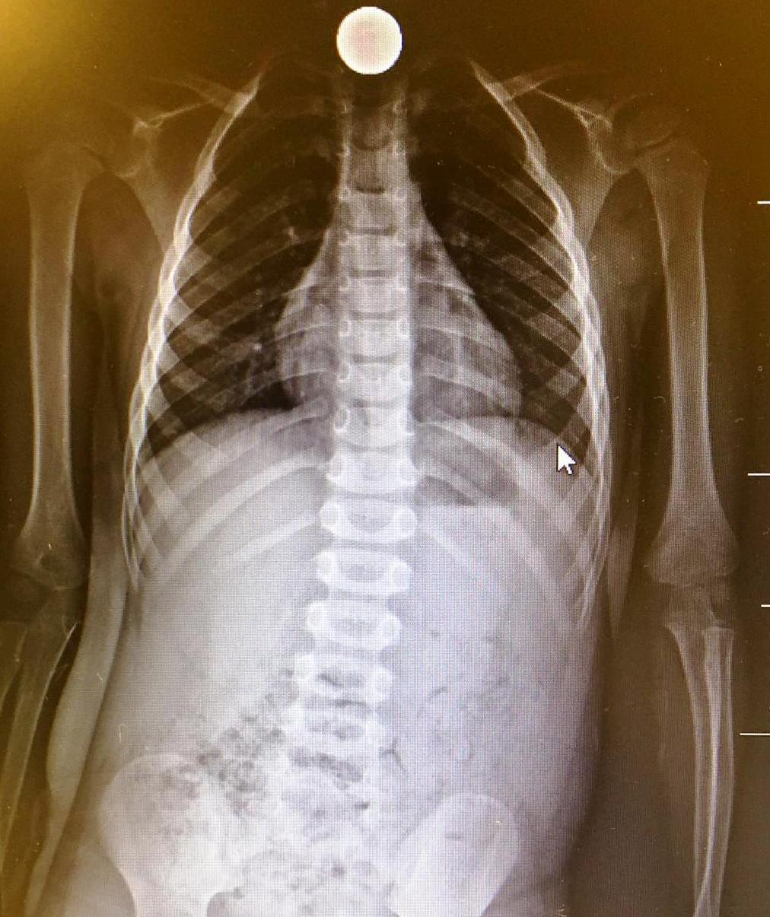

Durante la visita non emerge niente di particolarmente preoccupante, non vi erano segni di difficoltà respiratoria, in gola non si vede nulla. Quel sospetto, però, va assolutamente fugato. Per questo si procede subito con l’effettuazione di una lastra. Ed ecco che la moneta appare, nitida, “fra le tonsille e la laringe (uno spazio delicato di circa tre centimetri)”, come spiega Claudio Cavalli (Direttore UO Pediatria Aziendale), che aggiunge: “Era inserita a mo’ di salvadanaio, dritta dritta, come si vede dall’immagine radiologica. Bisogna agire in fretta, abbiamo pensato, perché se si mette di traverso, possono insorgere complicanze, anche serie”.

“Osservata la lastra e valutate le condizioni generali del bambino – che in quel momento era sofferente, piangeva, aveva scialorrea – abbiamo deciso di intervenire. La gastroenterologia di Cremona è dotata di tutte le strumentazioni pediatriche e delle competenze per agire anche sui bimbi molto piccoli”, afferma spiega Roberto Grassia (Responsabile del Servizio di Gastroendoscopia digestiva diretto da Federico Buffoli).

La Responsabile ammette: “Certo, sentivamo tutti il peso della responsabilità di intervenire su un bimbo così piccolo, alla fine è andato tutto per il meglio e il nostro paziente si è meritato il certificato di coraggio. A dire il vero per allentare la tensione, tutti gli operatori sanitari intervenuti hanno ricevuto il certificato di coraggio. La vera sorpresa è stata scoprire che si trattava di una moneta da 20 centesimi – conclude Grassia. Dalla radiografia e dalle dimensioni pensavamo fossero due euro, in proporzione all’esofago di un bimbo quasi un disco volante. Se per gli adulti questa procedura endoscopica può ritenersi routine, non è così per i più piccoli”.